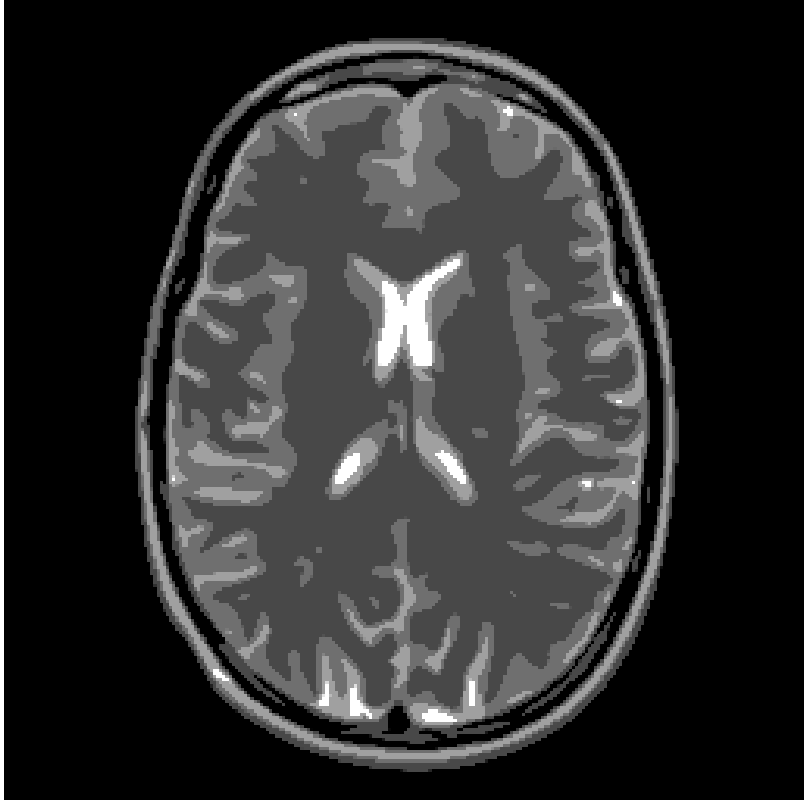

In this paragraph we test the performance of FNCR algorithm in reconstructing good quality images from highly under-sampled data. We focus on two synthetic images: the Shepp-Logan phantom (T1) (figure 2(a)), widely used in algorithm testing, and the Forbild phantom (T2) [21] (figure 2(b)), well known as a very difficult test problem.

Concerning the real MRI data we compare IL and FNCR algorithms in the reconstructions of the brain image (T3 test), represented in figure 8. We report in table 6 the results obtained by reconstructing the noiseless data undersampled by , , masks.